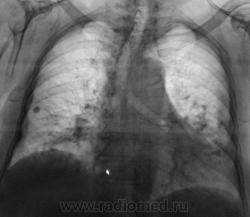

Фрагменты одиночной ткани справа.

Нижнедолевой бронх слева ампутирован. Достаточно болшая тень неправильно круглой формы в S9 (10) с неровным контуром,похоже, перибронхиальной инфильтрацией по нижней границей. Однако, при "ампутации" классического ателектаза нет, есть сниженная прозрачность... Очень скованно себя чувствую без боковой проекции. Есть?